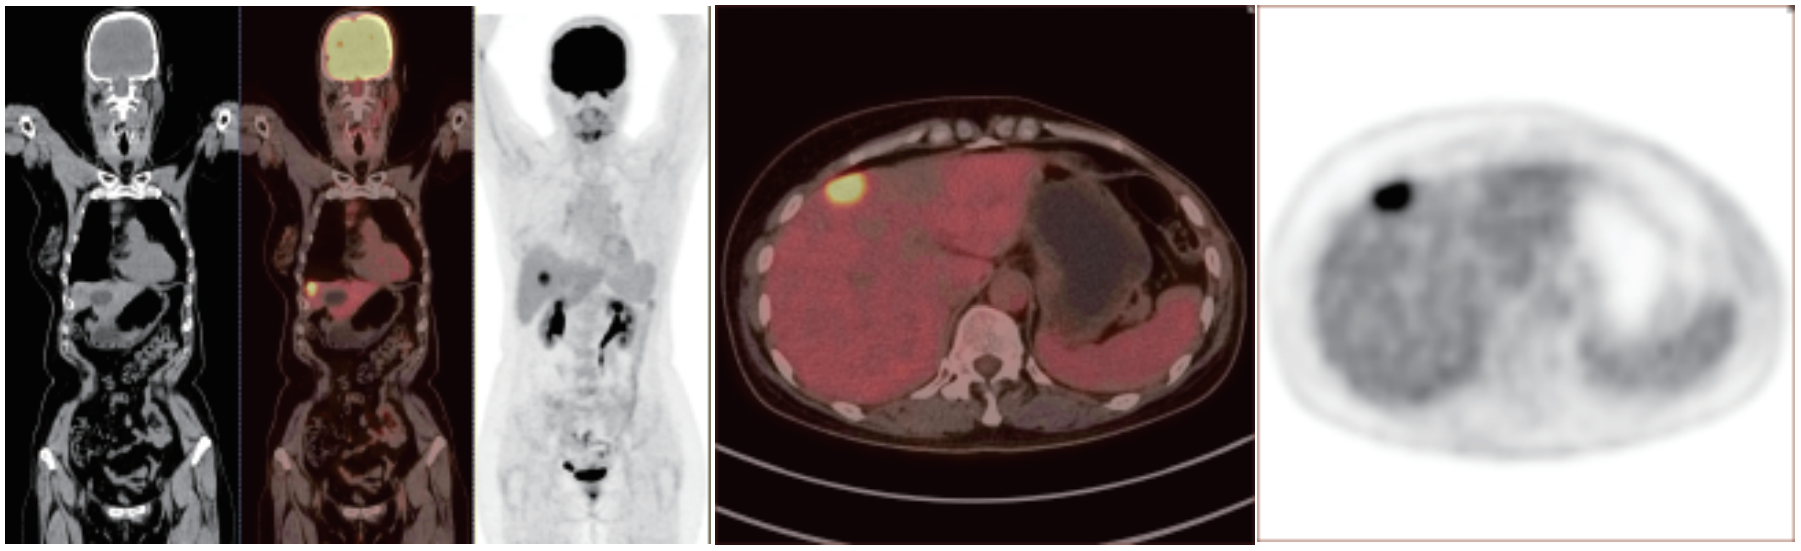

PET/CT 正電子發(fā)射及X射線計算機斷層成像系統(tǒng)

PET/CT在全身腫瘤的早期篩查、早期診斷、 良惡性鑒別、惡性腫瘤的分期、分級、尋找腫瘤原發(fā)病灶、評估療效及監(jiān)測腫瘤復發(fā)等方面具有重要價值。

相關(guān)病例成像圖